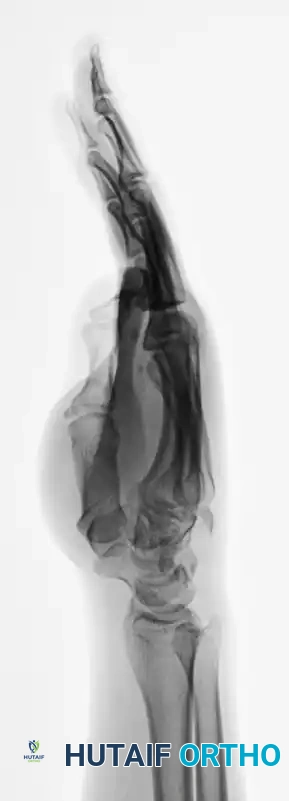

Standard posteroanterior (PA), lateral, and oblique radiographs are mandatory. However, the overlapping anatomy of the carpus can obscure subtle subluxations.

FIGURE 67-30 B-D: Posteroanterior, Lateral, and Oblique radiographic views demonstrating the dorsal dislocation of the fourth and fifth carpometacarpal joints.

> CLINICAL PEARL: Always obtain a true lateral radiograph of the hand. The metacarpal shafts should align perfectly parallel. Any dorsal divergence of the 4th or 5th metacarpal shafts relative to the 3rd metacarpal is highly indicative of a CMC dislocation. If plain films are equivocal, a CT scan is the gold standard for evaluating articular comminution and subluxation.